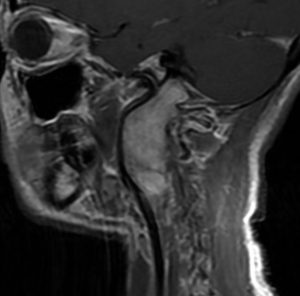

大きなもの

20年以上前の古い例です。今ではこんな大きな舌下神経鞘腫を見ることはあり得ません。